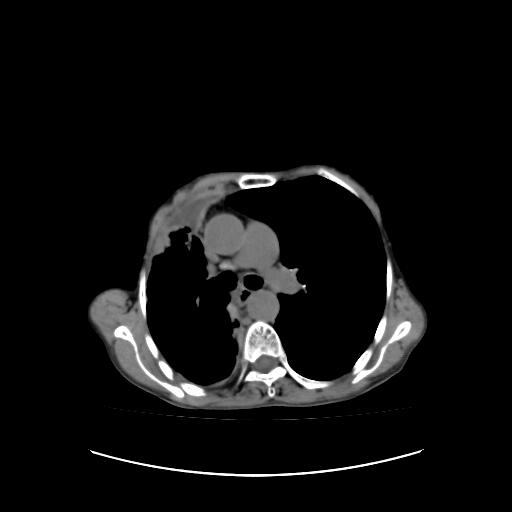

可见多发肺内病灶,且胸膜病灶较多有圆球状而非丘状,多考虑胸膜转移瘤伴胸腔积液,右侧胸廓缩小固定,且部分病灶呈丘状,尚不除外恶性胸膜间皮瘤伴肺内转移

右侧胸膜增厚,局部呈结节状增厚,右侧胸腔少量积液。双肺未见确切肿块影。纵隔未见淋巴结肿大。气管、支气管通畅。考虑右侧胸膜间皮瘤(恶性?)可能性大。不除外癌性胸膜炎。

恶性胸膜间皮瘤伴肺内转移可能性大;或胸膜、肺内均为转移瘤,左肺下叶亦见多发小结节影。

右侧胸廓塌陷,右侧胸膜广泛增厚并见多发胸膜结节,右侧少量胸腔积液并包裹。

右侧广泛胸膜增厚,局部呈结节状增厚,右侧胸腔少量积液。双肺未见确切肿块影。纵隔未见淋巴结肿大。气管、支气管通畅。考虑右侧胸膜间皮瘤(恶性?)可能性大。支持!

右侧胸膜转移瘤,原发灶可能就在在右肺,另外建议检查右侧乳腺.

右胸腔结节均考虑来自胸膜(部分来源于叶裂),考虑胸膜间皮瘤或转移瘤.